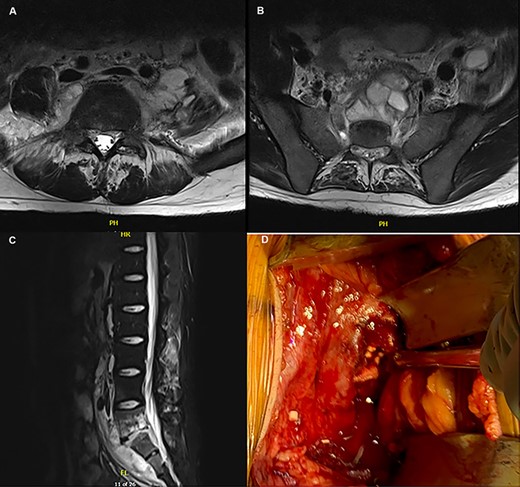

(A–C) MRI depicting the osteomyelitis, discitis and abscess involvement around L5/S1; (D) intraoperative picture of the L5/S1 disc space with placement of tobramycin antibiotic beads.

On follow-up it was discovered that he regularly consumed fresh cheese from Mexico (queso fresco). He had remained symptomatic with fevers. A Brucella antibody was sent and returned positive, therefore gentamicin was added and vancomycin discontinued. A repeat computed tomography scan obtained 4 weeks after the initial MRI showed progression of his infection. The patient was re-admitted to the hospital with spine and acute care surgeons consulted for surgical debridement. Using a left-sided anterior approach (Gibson incision), the retroperitoneum was entered. A large abscess cavity was noted from the L4-S1 pre-vertebral region, continuous with the psoas muscle. This was drained and debrided. He recovered from surgery but developed tinnitus with gentamicin; this was discontinued and the patient was discharged with a 6-week course of ceftriaxone, doxycycline and rifampin.

After 6 weeks of therapy, imaging showed progression of L5-S1 discitis/osteomyelitis and multiple abscess formations. He was admitted for a repeat incision and drainage through an anterior retroperitoneal approach with vascular, spine and acute care surgery. A large abscess was noted anterior to L5/S1, with the infection extending into the disc space. After drainage of the abscess and debridement, tobramycin antibiotic impregnated beads were placed in the disc space (Fig. 1D).